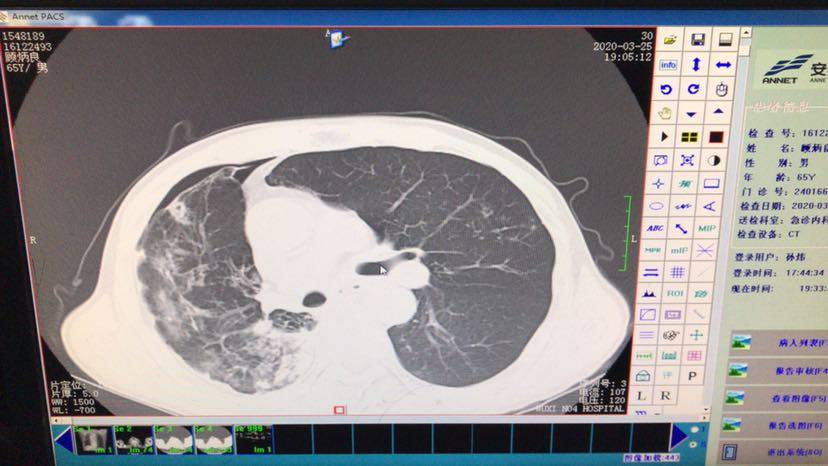

信达两针后出现肺炎,咳嗽加重,痰液加多,怕冷,出虚汗,体温35.9,没有发烧,吞咽不下去,喝水也会反出来,挂急诊拍片急诊说肺炎,只能立即消炎,挂了发票中的盐水2天还是咳嗽加重,突然痰液减少,主治不能收入病房,说先做痰培养,不能说是免疫肺炎,可能是细菌肺炎,可是快看病人坚持不下去了,不管是什么肺炎,还能用什么药,做什么处理呢?我该怎么办,求求大家,下面1到3图是这两天拍的,第4图是2月和现在的ct对比,大家看下

白细胞数量不是很高,医生可能看到中性粒细胞比例升高,怀疑是细菌感染的肺炎。影像学肺窗显示肿瘤对比可能是免疫造成的“假性进展”。可以先继续消炎试试,消炎的话会影响免疫药效果,免疫药要暂时先停掉。建议去咨询一下呼吸科或者肿瘤科